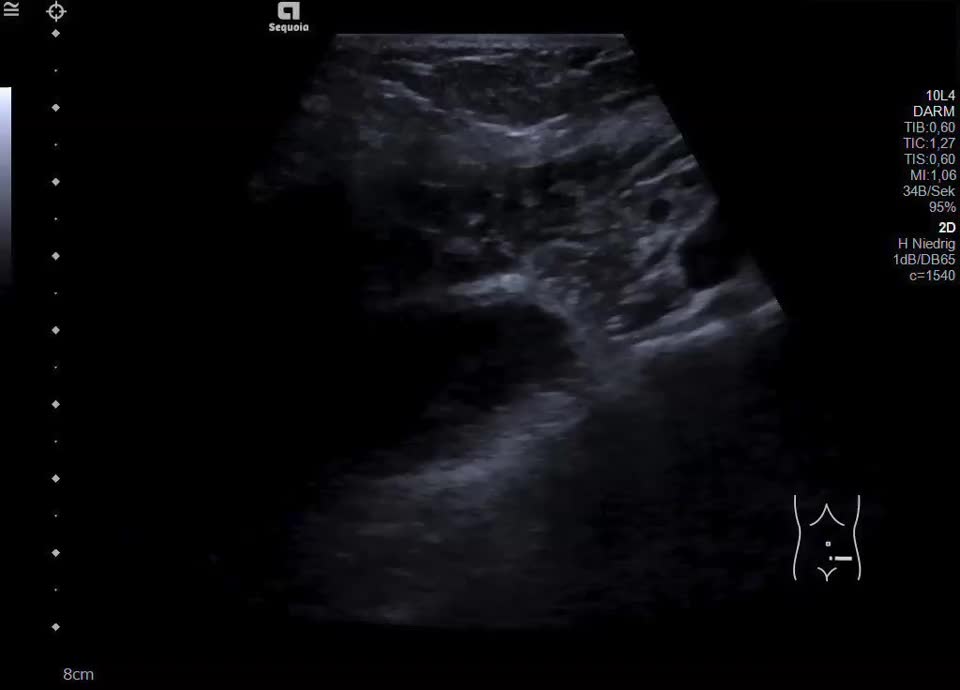

• Cystic ovarian tumor (video)

• Cystic ovarian tumor